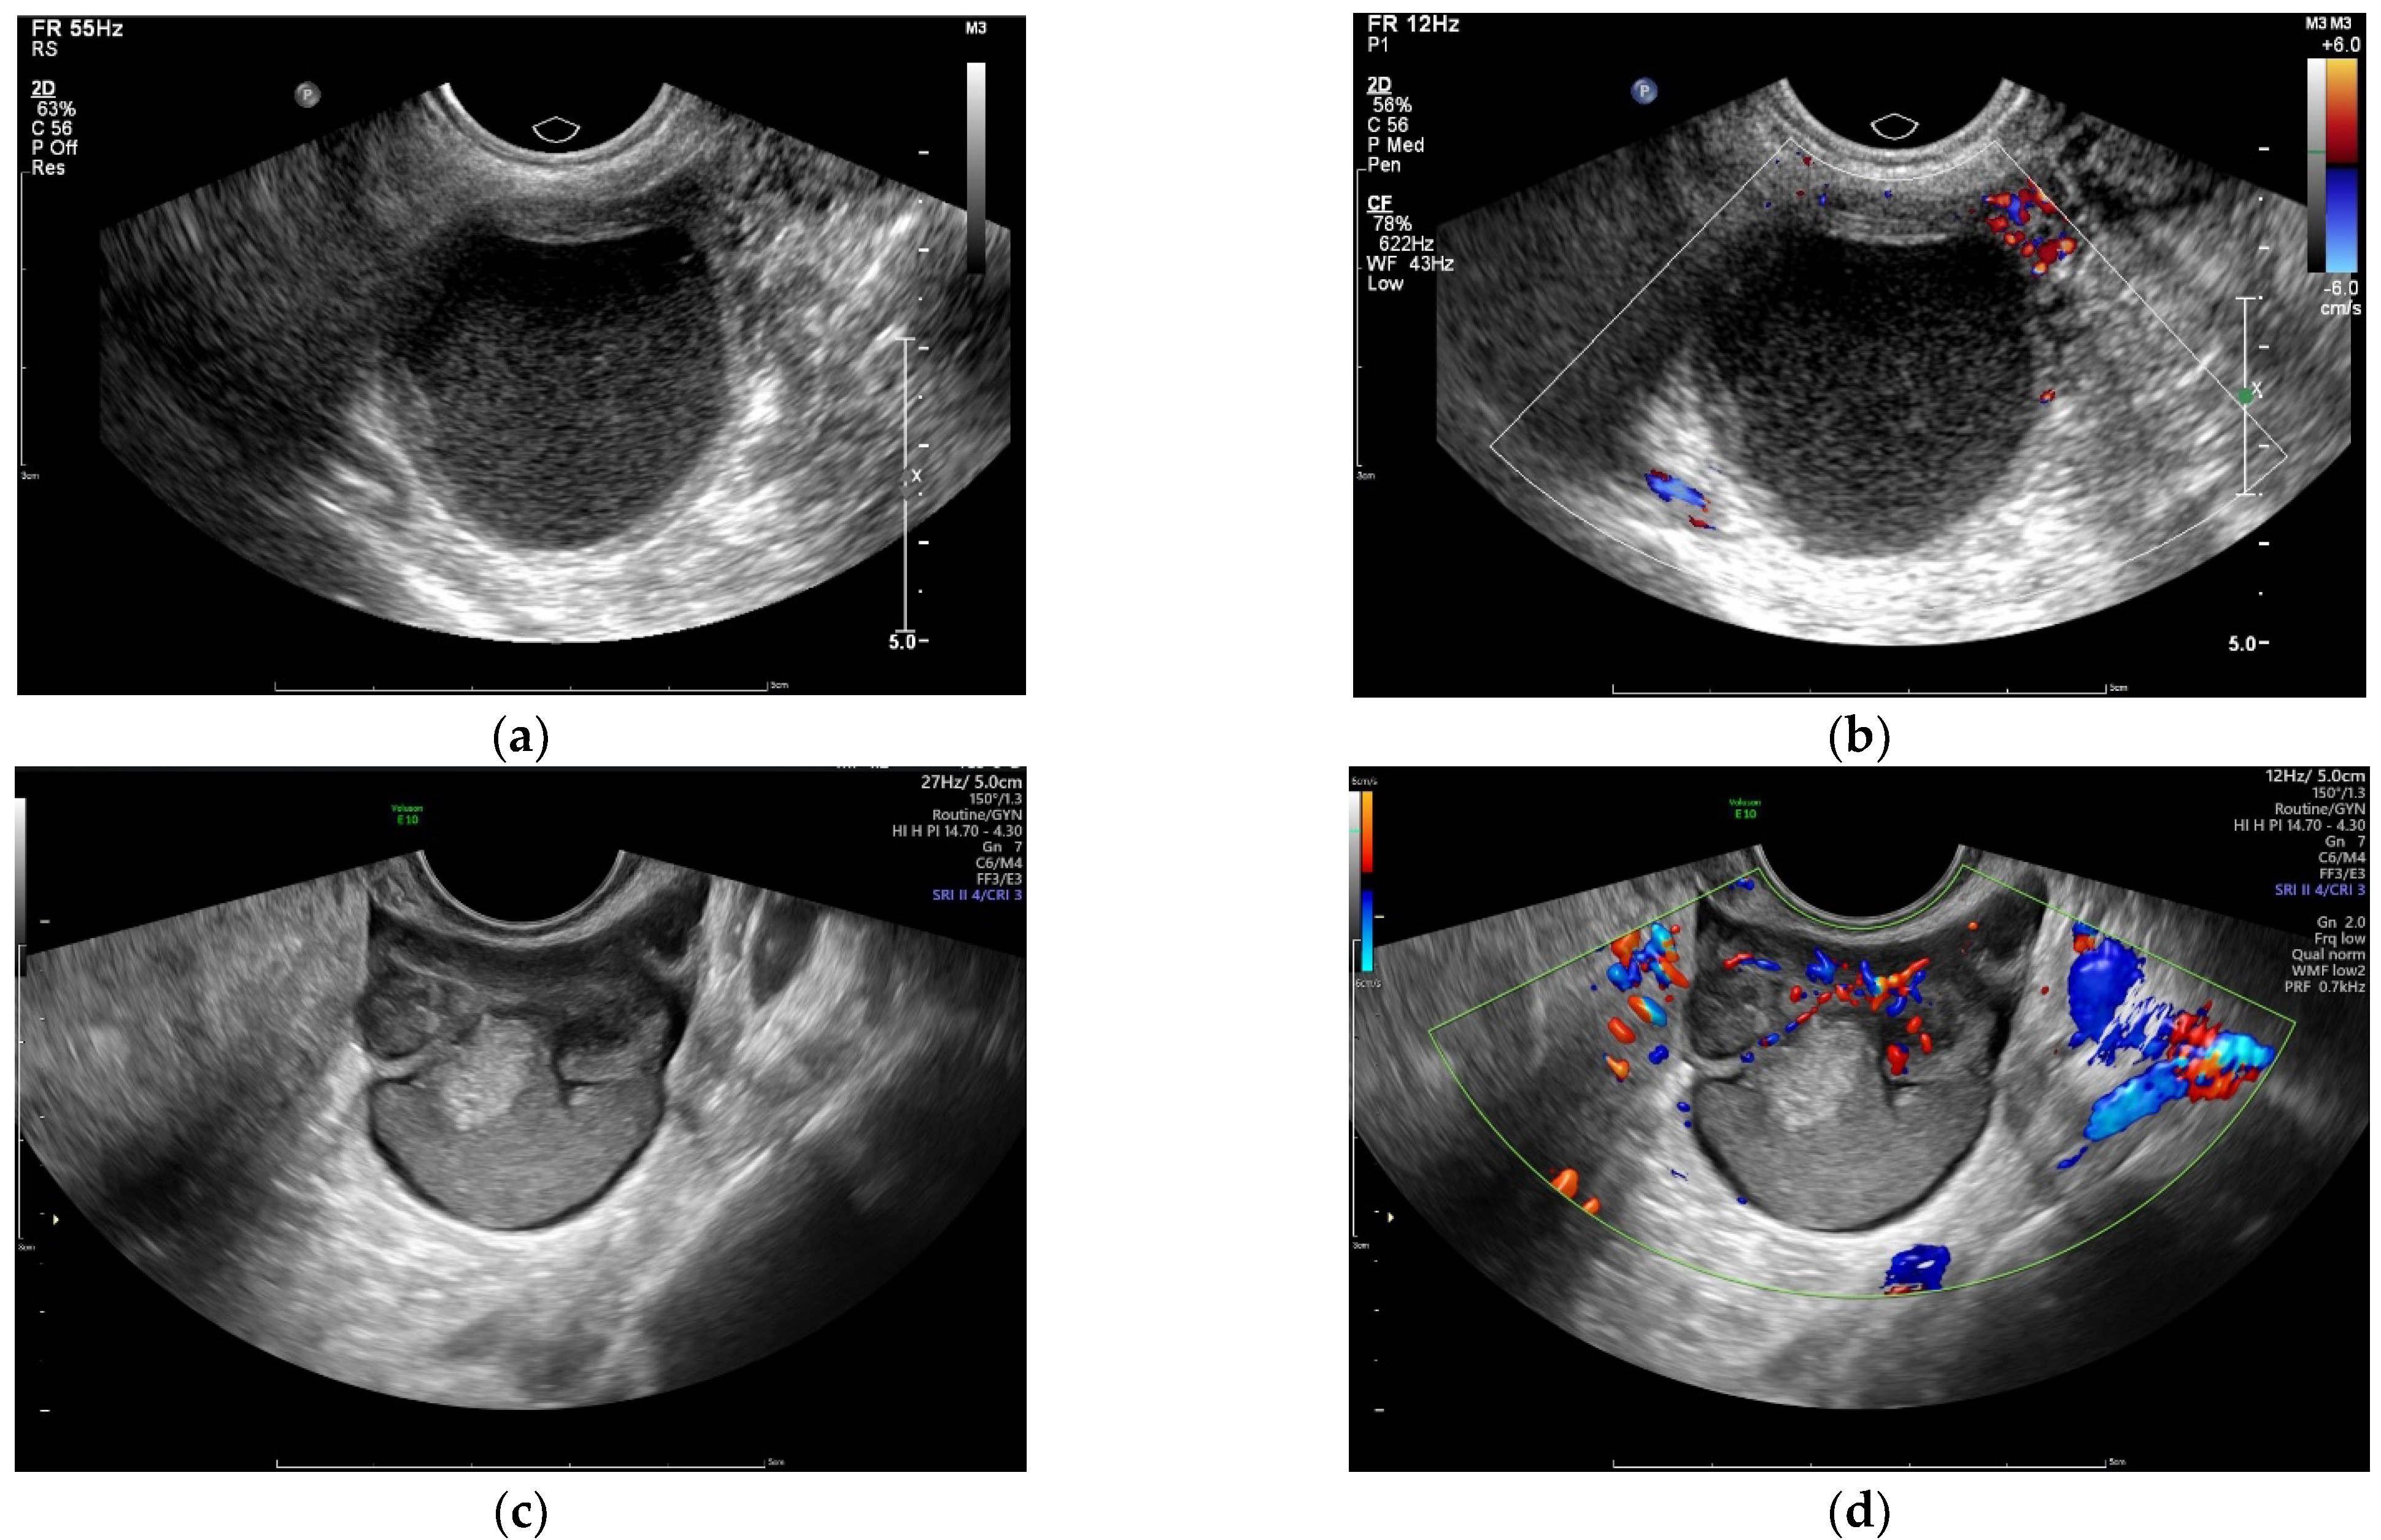

2.2. Sonography

3.3.1. Sonographic Parameters

| Endometrial cysts ** | Unilateral | 151 (91.5%) | 177 (54.3%) | <0.001 |

| Bilateral | 14 (8.5%) | 149 (45.7%) | ||

| Adenomyosis ** | 23 (13.9%) | 145 (44.5%) | <0.001 | |

| 142 (86.1%) | 181 (55.5%) | |||

| Pelvic endometriosis nodules ** | Yes | 14 (8.5%) | 96 (29.4%) | <0.001 |

| No | 151 (91.5%) | 230 (70.6%) | ||

| Unilocular cyst | Yes | 103 (62.4%) | 162 (49.7%) | 0.008 |

| No | 62 (37.6%) | 164 (50.3%) | ||

| Color Doppler flow | Without | 102 (61.8%) | 199 (61.0%) | 0.868 |

| With | 63 (38.2%) | 127 (39.0%) | ||

| Number of cavities * | 1 (1~2) | 2 (1~3) | 0.007 | |

| Maximum cyst diameter * (mm) | 52 (40~67) | 57 (43~72) | 0.013 | |